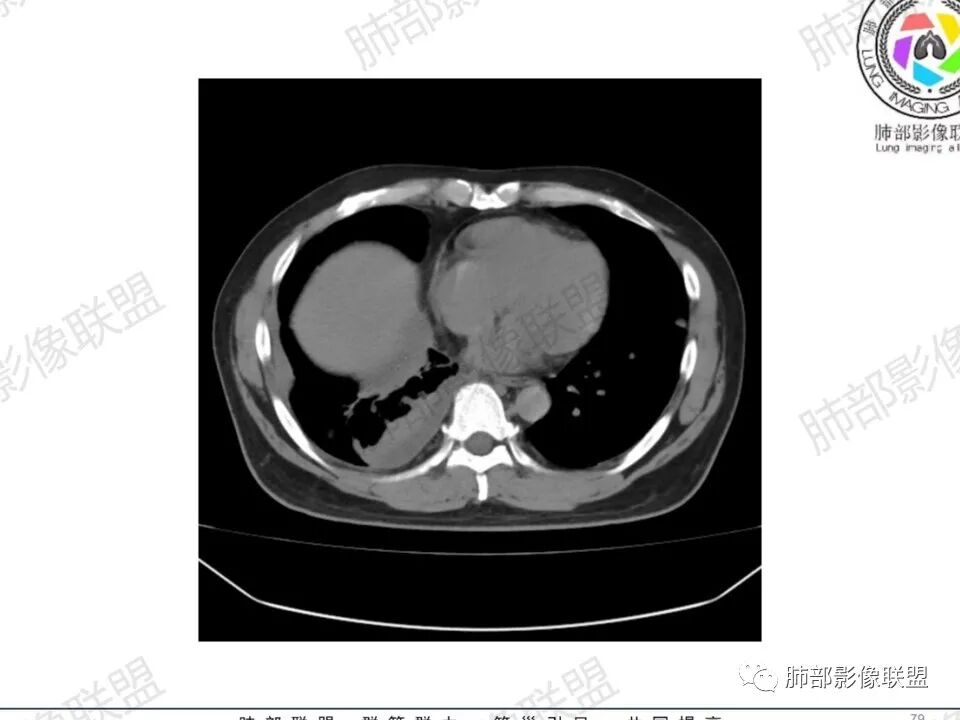

双肺多发结节,胸膜下为主,部分可见空洞。左肺上叶尖后段结节较大,分叶毛刺,周围可见长条索及小斑片影,内空洞比较光滑,内侧壁可见支气管通过。右肺下叶后基底段不张实变,后侧积液,右侧水平裂积液,右侧膈胸膜纵膈胸膜增厚积液,右侧侧胸膜肥厚,考虑1:一元金葡。2二元:金葡,左肺上叶结核。

中年男性,左手中指及胸壁疼痛伴发热来诊,影像见双肺多发结节,胸膜下分布为主,部分结节可见空洞,边缘模糊。左肺上叶尖后段结节较大。右肺下叶后基底段不张实变,右侧叶间裂及右侧胸腔积液,右侧侧胸膜肥厚。考虑金葡菌感染,血播SPE。

两肺多发结节空洞,随机分布,右肺下叶部分病灶实变并胸膜腔少量积液,有皮肤破溃,手指疼痛,发热,考虑感染性变,金葡可能性大。